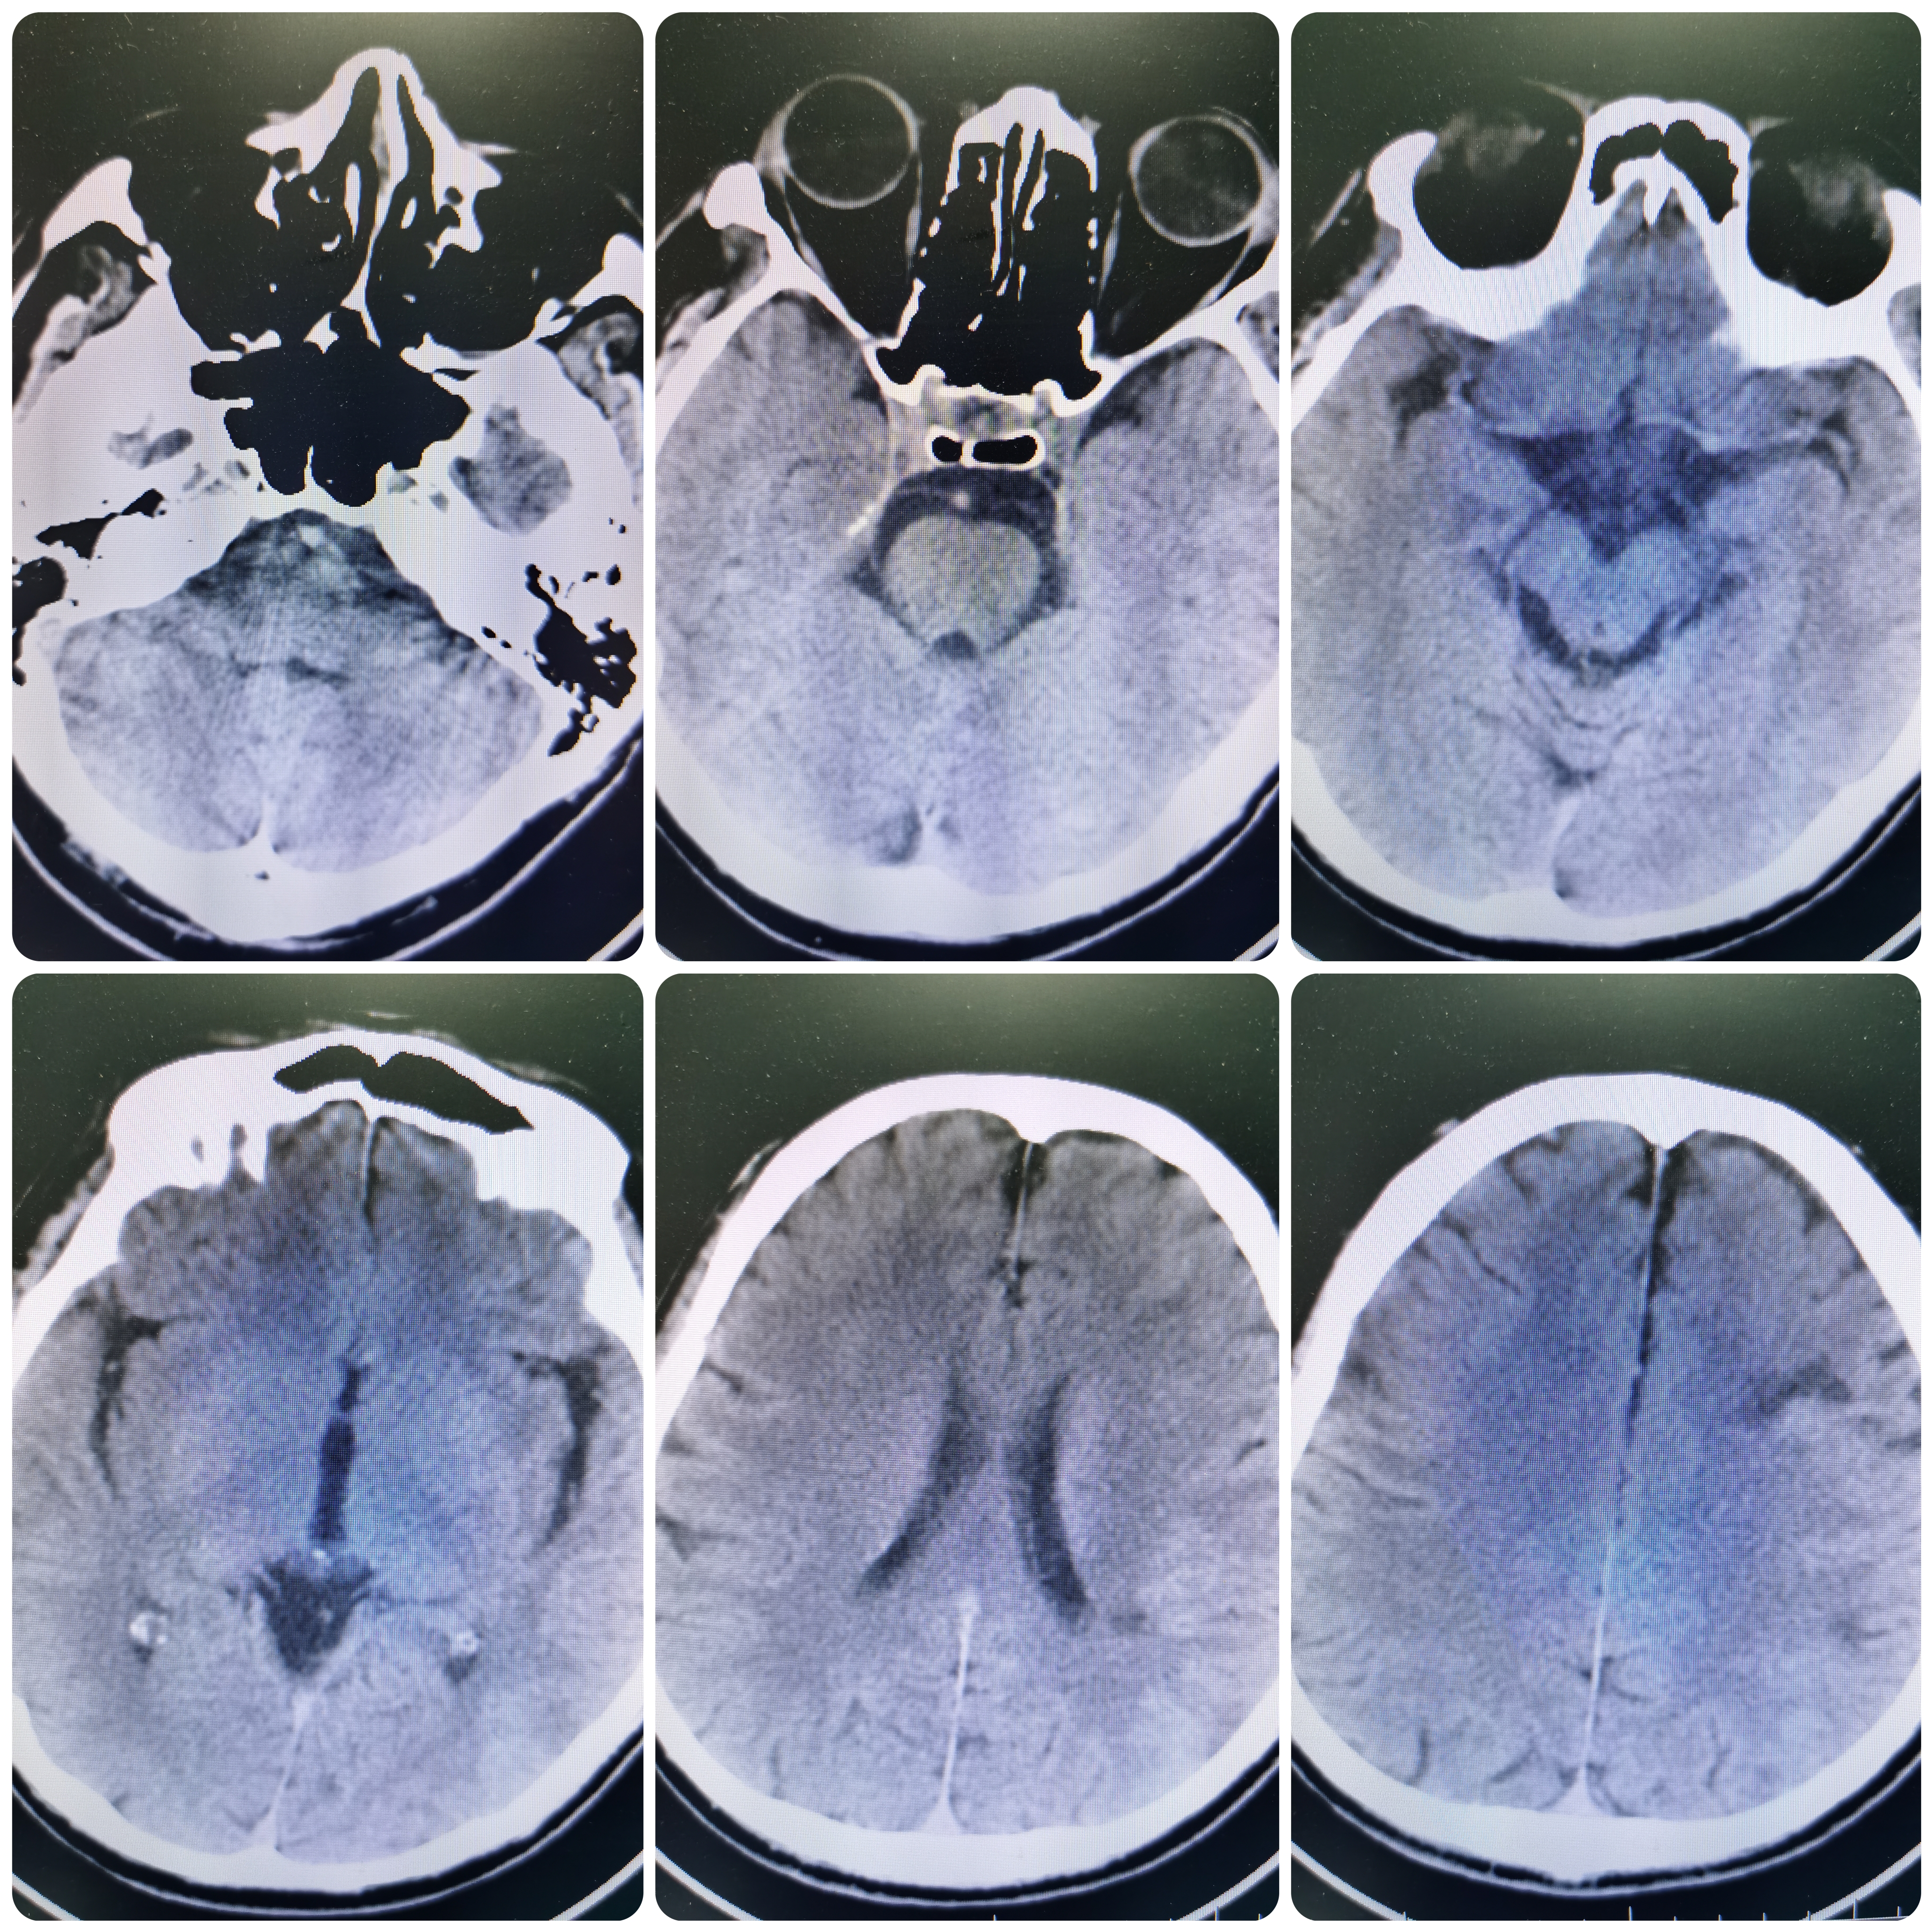

急诊头颅CT示左侧额叶低密度灶。

完善核磁DWI示左侧额颞顶枕叶,左侧基底节区 左侧半卵圆中心多发新近脑梗死。